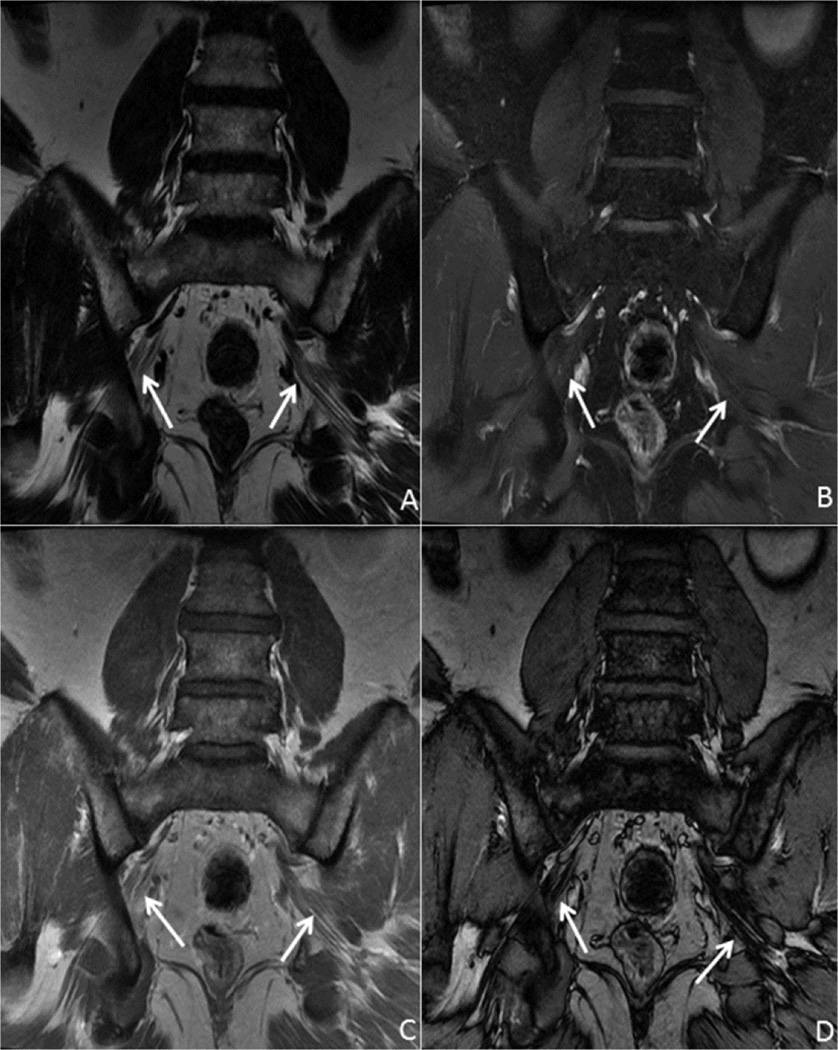

Fig. 1 demonstrates a normal lumbosacral plexus with excellent visualization of the sciatic nerve, as well as delineation of the internal architecture. With one acquisition, a routine T1 weighted fat suppressed image is obtained along with a water suppressed (fat) image and in and out of phase images.

41 year old male with normal anatomy. Coronal T1 IDEAL post contrast images of the lumbosacral plexus, specifically the sciatic nerves (arrows): A—fat only image clearly delineates the course of the sciatic nerves, as well as the internal architecture; B—water only image demonstrates no abnormal enhancement in the sciatic nerves; C (in-phase) and D (out-of-phase) images can be useful in evaluation of marrow abnormalities.